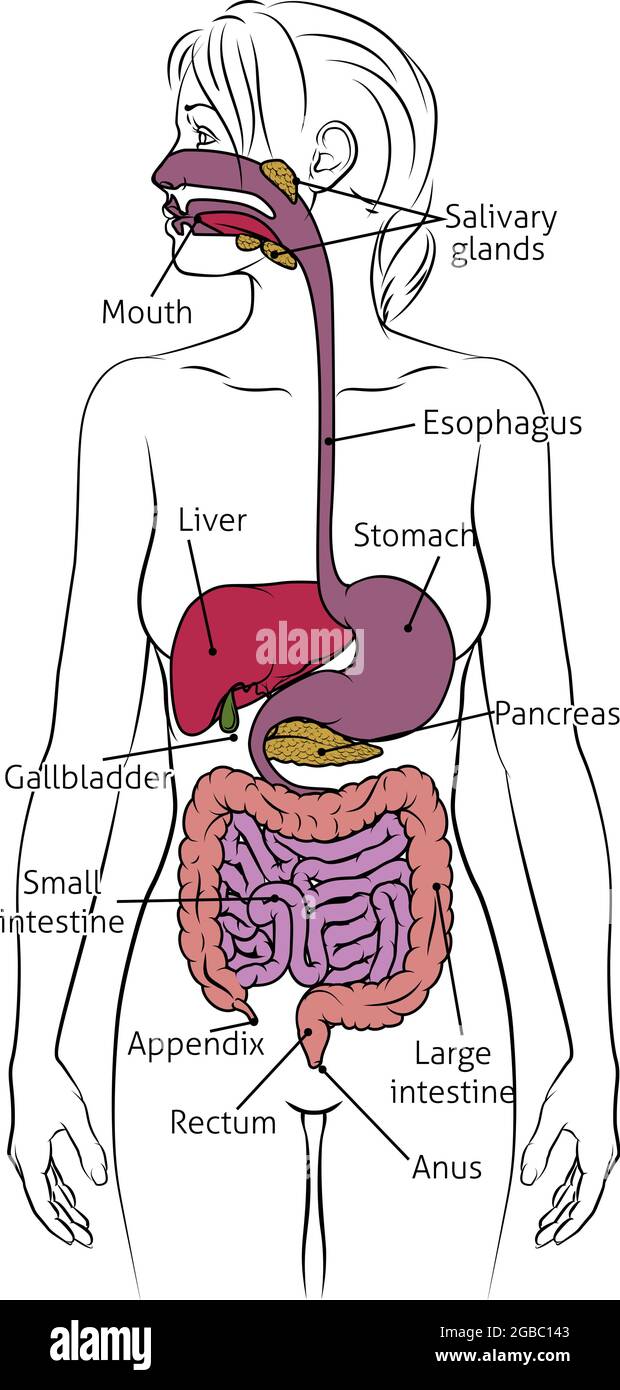

Système digestif humain Femme Schéma anatomique Illustration de Vecteurhttps://www.alamyimages.fr/image-license-details/?v=1https://www.alamyimages.fr/systeme-digestif-humain-femme-schema-anatomique-image437284739.html

Système digestif humain Femme Schéma anatomique Illustration de Vecteurhttps://www.alamyimages.fr/image-license-details/?v=1https://www.alamyimages.fr/systeme-digestif-humain-femme-schema-anatomique-image437284739.htmlRF2GBC143–Système digestif humain Femme Schéma anatomique